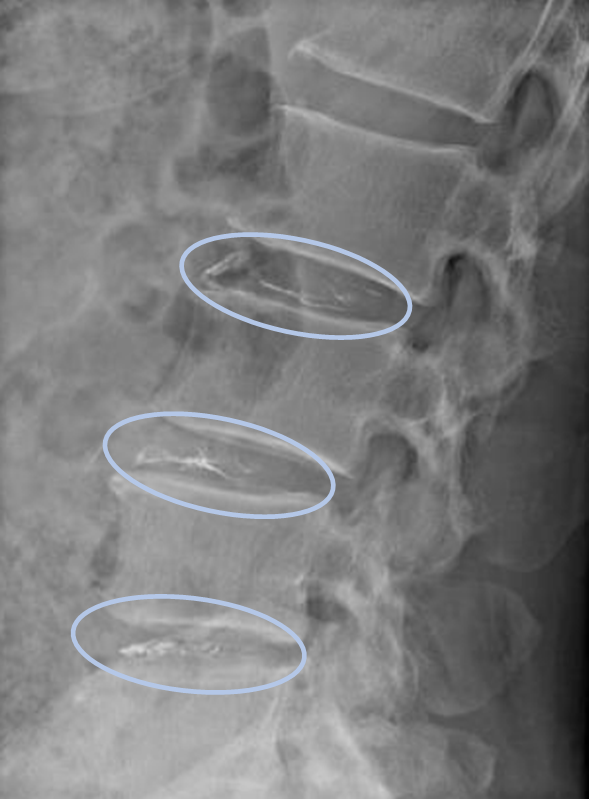

DiscoGelを入れた後の画像になります。